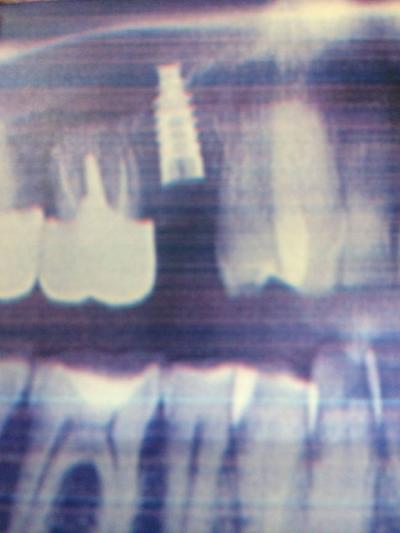

Un implant est une sorte de vis en titane, fixée dans l'os comme la racine d'une dent naturelle.

C'est pourquoi, le dentiste adapte la longueur, le diamètre et la forme au cas clinique grâce à un examen radiologique performant: 3D ou scanner.

L'implantologiste va, à l 'aide de forets de diamètre adpaté, préparer la place dans l'os. L'implant pénétre dans l'os en forçant légèrement. Il est ainsi stabilisé. Après la pose de l'implant va avoir lieu la phase d'ostéo-intégration. En effet l'implant, contrairement à la dent, est totalement fixe, c'est-à-dire ankylosé dans l'os. La mise en charge de l'implant est généralement différée pour permettre la phase d'ostéo-intégration (de plusieurs semaines à plusieurs mois). Par la suite, une couronne sera mise sur cet implant qui se comportera comme une racine artificielle.